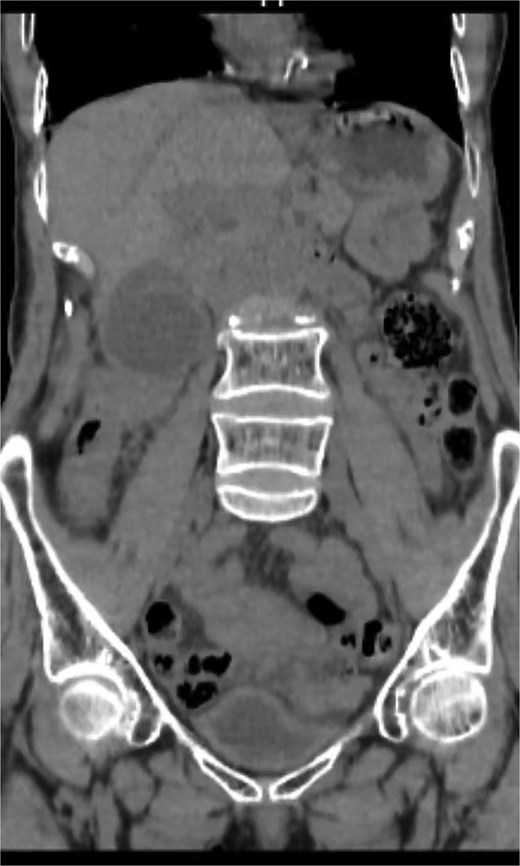

An 82-year-old female presented to the emergency department with a 2-day history of right upper quadrant pain accompanied by nausea and vomiting. The patient was hunched and thin, with a body mass index of 15.0 kg/m2 (Fig. 1). Physical examination revealed abdominal tenderness and a positive Murphy’s sign. Routine blood examination showed a white blood cell count of 16.5 × 10 [5], C-reactive protein of 3.83 mg/L, and normal liver function and electrolytes. A non-contrast abdominal computed tomography (CT) scan (Fig. 2) and gallbladder US (Fig. 3) were performed. We administered analgesics and antibiotics for 24 hours based on US and CT findings indicating impacted stones in the neck of the gallbladder. However, the patient’s symptoms of persistent abdominal pain did not improve, prompting us to proceed with laparoscopic exploration. During the operation, a necrotic gallbladder was identified within the confined space of the abdominal cavity (Fig. 3). Subsequently, intraoperative puncture decompression of the gallbladder was performed, followed by exploration via manipulation and rotation of the gallbladder using laparoscopic instruments (Fig. 4). The gallbladder was found to be completely mobile and had undergone a 360°clockwise torsion (Fig. 5). We successfully performed a laparoscopic cholecystectomy and pathological examination showed acute gangrenous cholecystitis. The patient was discharged on the fourth postoperative day.